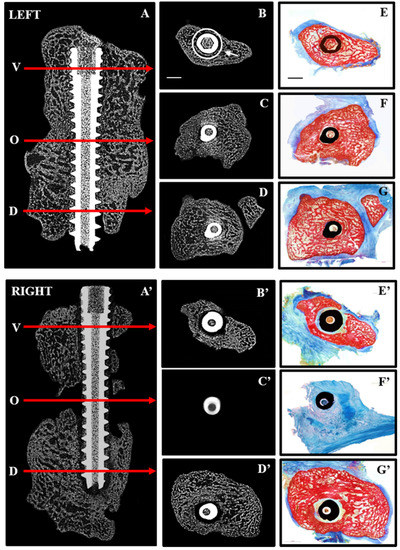

Figure 3.

Repair after immediate (LEFT) and delayed (RIGHT) fixation: 2D micro CT images are shown in the sagittal plane (A,A’) indicating the position along the screw (arrows) at which transaxial 2D images are shown for the volar (V,B,B’), osteotomy site (O,C,C’) and dorsal (D,D,D’) aspects of the radiocarpal bones. Corresponding histological sections from the same levels (E–G,E’–G’) were stained with Alizarin red and Methylene blue to distinguish mineralized (red) from soft (blue) tissue. Complete bridging occurred with immediate fixation (A,C) whereas little bone was seen in the osteotomy site (A’,C’) with delayed fixation. Histological sections confirmed the presence of bone in the osteotomy site with immediate fixation (F) and its absence with delayed fixation (F’). Arrow (B) points to ROI used for quantitative micro CT analyses and scale bars (B,E) represents 2 mm.

In contrast to immediate fixation (IF) (Figure 3A–G), where bone was seen adjacent to the screw along its entire length, delayed fixation (DF) resulted in soft tissue along the length of the screw (Figure 3A’–G’). This is most noticeable on the histological sections where bone is red and soft tissue blue. Quantitative micro CT (Figure 4) revealed significantly less bone (BV/TV) adjacent to the screw at the osteotomy site (white circle in Figure 3B) with DF compared with IF.